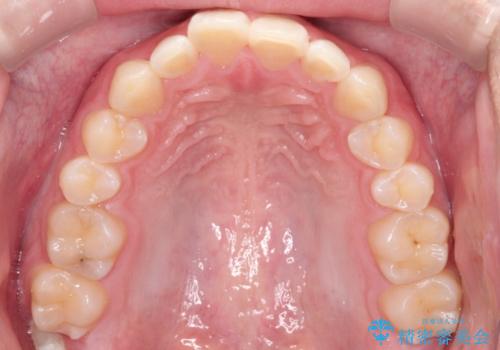

上の歯が全体的に下の歯の位置に比べると前方に位置しており、上の前歯が前方に傾斜している状態でした。

上の奥歯を後方に移動して、隙間を作り、前歯を引っ込める計画としました。